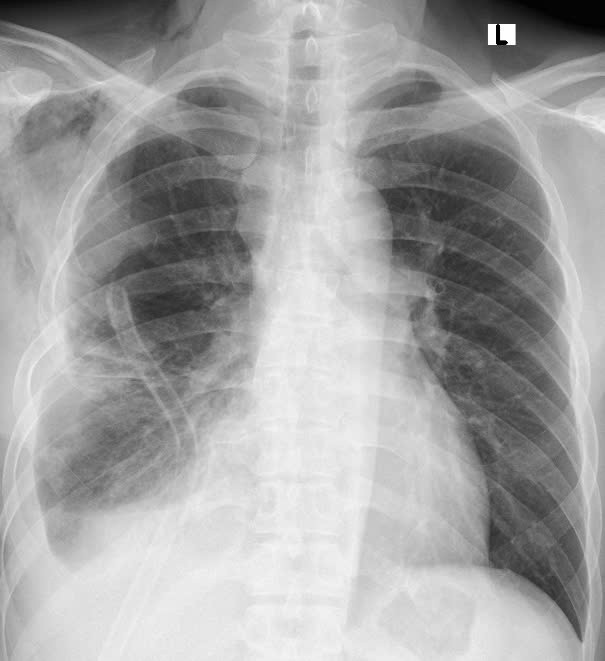

Hình ảnh phim chụp X.quang trước và sau khi phẫu thuật. (Hình trước phẫu thuật bên trái). Ảnh BVCC

Qua thăm khám và chụp cắt lớp vi tính lồng ngực, các bác sĩ phát hiện khối u trung thất khổng lồ nằm lệch trong khoang màng phổi phải, chèn ép gây xẹp gần như toàn bộ phổi phải, đẩy lệch cơ hoành. Kết quả sinh thiết xác định đây là u bao sợi thần kinh Schwannoma - Một loại u lành tính hiếm gặp xuất phát từ bao thần kinh nhưng kích thước "khủng" hiếm thấy. Khối u xâm chiếm khoang ngực, gây xẹp gần như toàn bộ phổi phải

"Trong quá trình phẫu tích, khối u dính chặt vào mạch máu trung thất, có vỏ mềm và tăng sinh nhiều mạch máu gây chảy máu ồ ạt. Ê kíp đã có sự chuẩn bị từ trước, xác định ca mổ có nguy cơ chảy nhiều máu, bệnh nhân được chuẩn bị sẵn sàng máu để truyền. Trong mổ bệnh nhân được truyền bù 02 đơn vị máu, đồng thời ê kíp nhanh chóng kiểm soát tình hình bằng kỹ thuật kiểm soát cuống mạch nuôi khối u và khâu buộc thắt mạch cầm máu. Việc tiếp cận và bóc tách đòi hỏi độ chính xác tuyệt đối để tránh tổn thương các cơ quan quan trọng như tim, phổi và mạch máu lớn. Sau 02 giờ căng thẳng, khối u khổng lồ đã được lấy trọn vẹn ra ngoài, phổi phải giãn nở trở lại, hồi phục hình thái và chức năng bình thường", TS.BS Ngô Gia Khánh - Trưởng khoa Phẫu thuật Lồng ngực và Mạch máu chia sẻ.